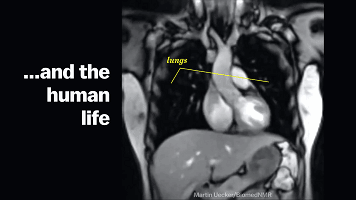

呼吸系统

这里排除体力和激烈运动的原因

我们会发现,在开啪之前我们的呼吸就

开始变得有那么一点急促,但这个时候我们

还是可以自我调节控制呼吸节奏来调整状态

这是由于中枢神经的兴奋,使你的血压开始

升高、肌肉收缩、身体代谢也增快,这

直接导致了氧气的加速消耗,所以氧气

摄入会需要提高,从而导致了你呼吸急促